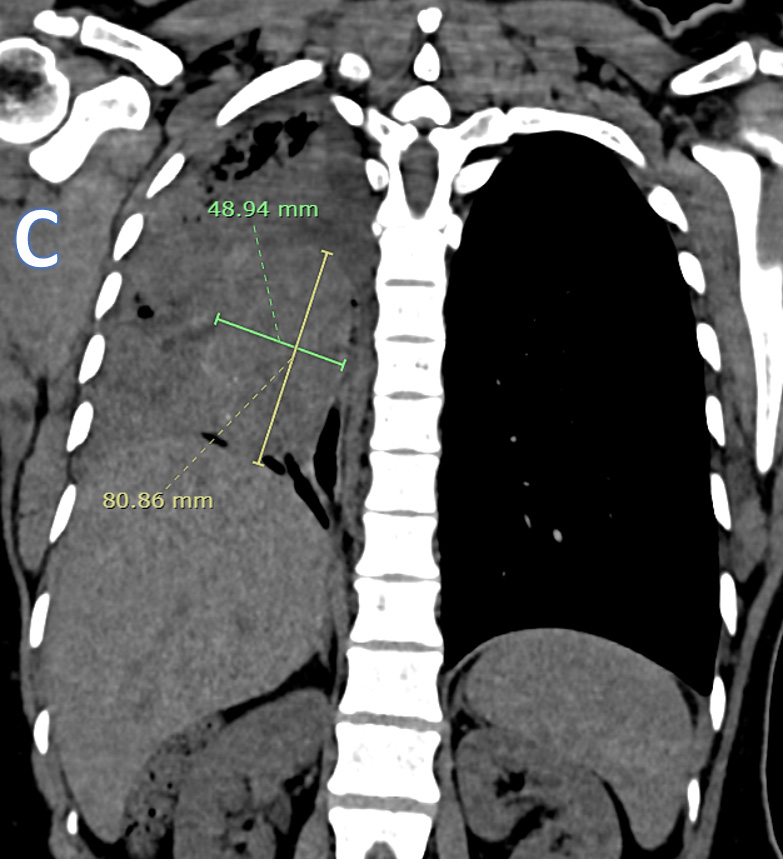

C – CORONAL CT THORAX

Ovoid heterogeneously isodense mass lesion with multiple tiny peripheral specks of calcifications in the right hemithorax with endobronchial extension.

B – Axial CT thorax (soft tissue and lung window images)

• ARROW: Soft tissue density endobronchial mass lesion in the right main bronchus.

• STAR: Collapsed right lung and hypodense  fluid in the right hemithorax.